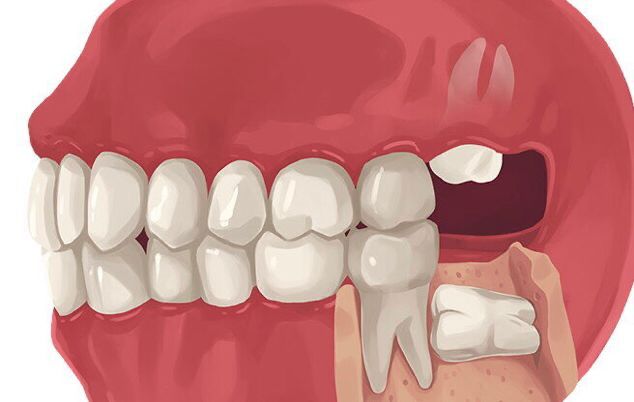

Como sua formação e nascimento podem ocorrer apenas na maioridade, é possível que não encontrem espaço para irromperam sem causar problemas.

Nestes casos, a remoção pode ser a alternativa.

- Movimentação dos dentes: caso o siso não encontre espaço, ele poderá ficar retido no osso, empurrando outros dentes.